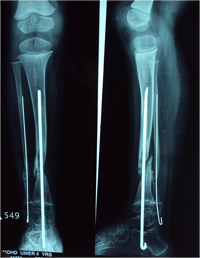

Also known as congenital "Anterolateral Bowing of Tibia" or CPT is a rare condition seen in infants and children. The tibia is bowed and the apex of the deformity in anterior and lateral in the sagittal and coronal plane respectively. Incidence is 1: 140,000. This type of bowing is pathognomomic of CPT or Congenital Pseudarthrosis of tibia, leading to a recalcitrant non-union of the tiba and fibula. Almost 50% of cases are associated with Neurofibromatosis type I or fibrous dysplasia. The deformity may be present at birth or occurs as a painless stress fracture when child starts to walk. The typical site of deformity is in the lower third of the leg and both tibia and fibula may be involved. Radiographs reveal typical bowing and the tibia may have sclerotic edges, cortical tapering, cyst formation and sometimes obliteration of meduallary cavity. CPT that Require Treatment

Rush Rodding Periosteal Grafting

Newer Fassier - Duval rod in an older child. About CPTCPT is a disorder of the tibia where there is a propensity for recurrent fractures, poor healing of bone and need for multiple operations. Current methods of treatment of CPT have evolved to give much more consistent results than previously possible. Special methods are available to achieve union. |